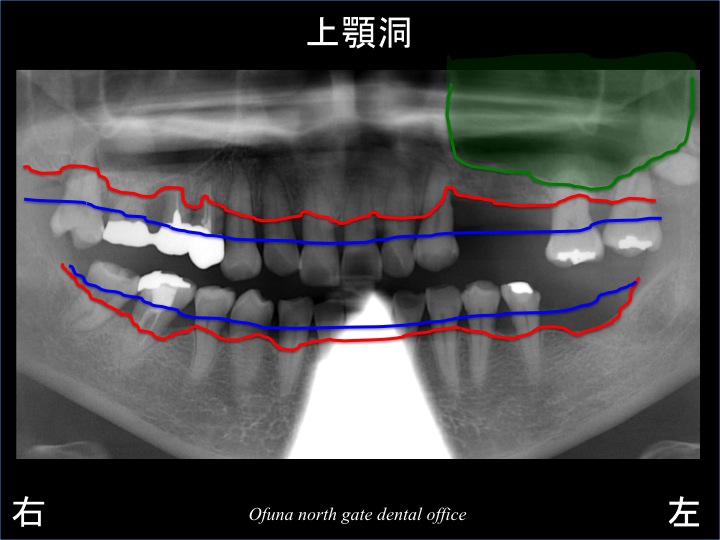

いつものように 骨吸収の状態を分かりやすくするために

骨吸収の状態を線で書いたのが以下になります。

青線が骨吸収を起こす前の骨の位置です。

赤線は、現在の骨の位置です。

骨が吸収してしまったのが分かるかと思います。

緑線は上顎洞です。

上顎洞(緑線の上方)は空洞です。

骨ではなく、穴が開いているのです。

以下のレントゲンは、骨吸収の状態と上顎洞をさらに分かりやすくあらわしたものです。

緑色の部分は空洞ですので、

骨が存在するのは赤線と緑色の間だけになります。

骨の高さが非常に少ない状態です。

同部分は、ソケットリフト法 とGBR法(骨増大法) を併用してインプラントを埋入する計画を立てました。